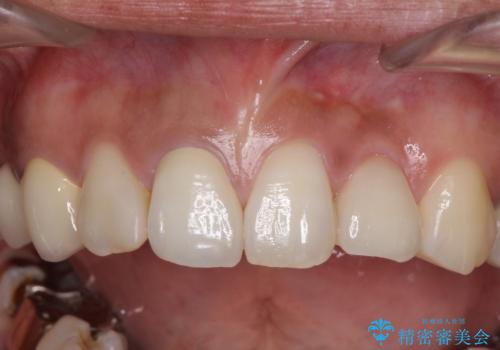

歯の裏側を一層だけ削り、接着力に頼ったブリッジを装着してはみたものの、案の定咬む力に負けて、接着が剥がれてしまっていました。

歯を削る量は増えますが、より長い期間再治療なく使用していただくことを最優先に考え、フルカバレッジのオールセラミックブリッジにて補綴することとしました。

前歯の裏側の接着面は、隙間ができていたことにより、汚れがたまるだけでなく、むし歯にもなっていました。

我々としては、治療により状態が悪化することだけは避けたいと考えているため、歯全体を覆うクラウンにすることで、より長持ちする治療を提供いたしました。